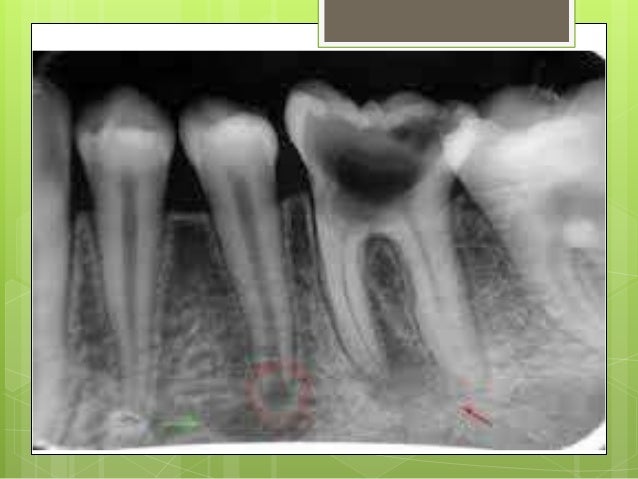

PRIMERA IMAGEN: Imagen radiolucida compatible con caries oclusal UD#36 avanzada con compromiso de dentina, pulpa y lesión en furca. Imagen radiopaca compatible con espacio del ligamento periodontal ensanchado. Imagen radiopaca compatible con cresta alveolar reducida UD 34, 35 Y 36. Imagen radiolucida compatible con reabsorción radicular proximal UD 34, 35 y 36

PRIMERA IMAGEN: 1) unidad dentaria #36. Imagen radiolúcida compatible con caries dental oclusal, que muestra compromiso de esmalte, dentina y pulpa. Imagen radiolúcida a nivel del #36 compatible con lesión de furca.

2) imagen radiolúcida compatible con espacio del ligamento periodontal ensanchado.

3) Imagen radiolúcida a nivel del ápice de las unidades dentarias #35 y #36 compatible con lesión apical.

4) imagen radiopaca compatible con cresta alveolar reducida en unidades dentarias #34, #35 y #36.

Primera Imagen: Imagen radio lucida a nivel coronal compatible con caries oclusal avanzada en la UD 36, también presenta un absceso a nivel apical en la UD 35 y 36 y un ensanchamiento del ligamento periodontal

PRIMERA IMAGEN

Imagen radiolúcida (UD #36) a nivel coronal compatible con caries dental oclusal.

Imagen radiolúcida (UD #36 y #35) a nivel del apice compatible alguna lesión apical y ensanchamiento del ligamento periodontal

• Primera imagen: Radiografía periapical de la zona postero inferior donde se observa a nivel de la corona de la UD#36, pérdida de sustancia dentaria debido a un proceso carioso. A nivel apical se observa una zona radiolucida de bordes irregulares compatible con absceso periapical crónico.

La zona radiolucida periapical a nivel del ápice de la UD#35, que se puede confundir con una osteítis rarificante, pero se ven los elementos periodontales, lo que sugiere sea la papila dental. La flecha verde señala al agujero mentoniano.

Primera imagen: imagen radiolúcida de bordes irregulares, a nivel del segundo premolar inferior izquierdo 35, compatible con lesión apical, se observa imagen radiolúcida de bordes irregulares a nivel coronal de primer molar inferior derecho 36, compatible con lesión de caries profunda, se observa también un ensanchamiento del espacio del ligamento periodontal e imagen radiolucida de bordes irregulares a nivel de la raíz mesial compatible con lesión apical.

1era imagen: se observa la unidad dentaria #36, es una imagen en donde se ve una zona radiolucida a nivel de la coronal la cual es compatible con una caries, en donde se muestra que el esmalte, dentina y pulpase encuentran comprometidos. A nivel del apice de las unidades dentales #35 y #36 se observa lesiones apicales.